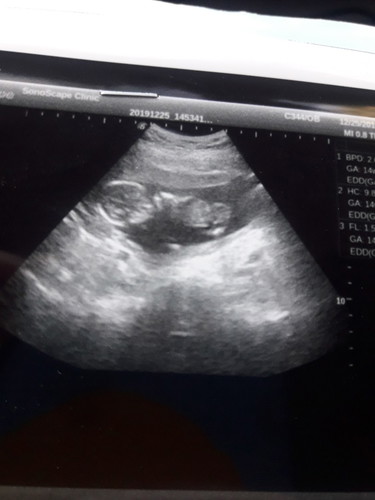

แม่ท่านไหนมีประสบการณ์ ลูกส่วนนำอยู่ท่าก้นบ้างคะ อายุครรภ์14+3 แล้วลูกจะหันหัวนำไหมอันตรายไหมคะ ท้องแรกค่ะ

เพิ่ง14วีคเองค่ะ น้องหมุนตัวได้ตลอด ปกติน้องก็อยุ่ท่าขวางท่าก้น จะกลับหัวช่วงใกล้คลอดค่ะ